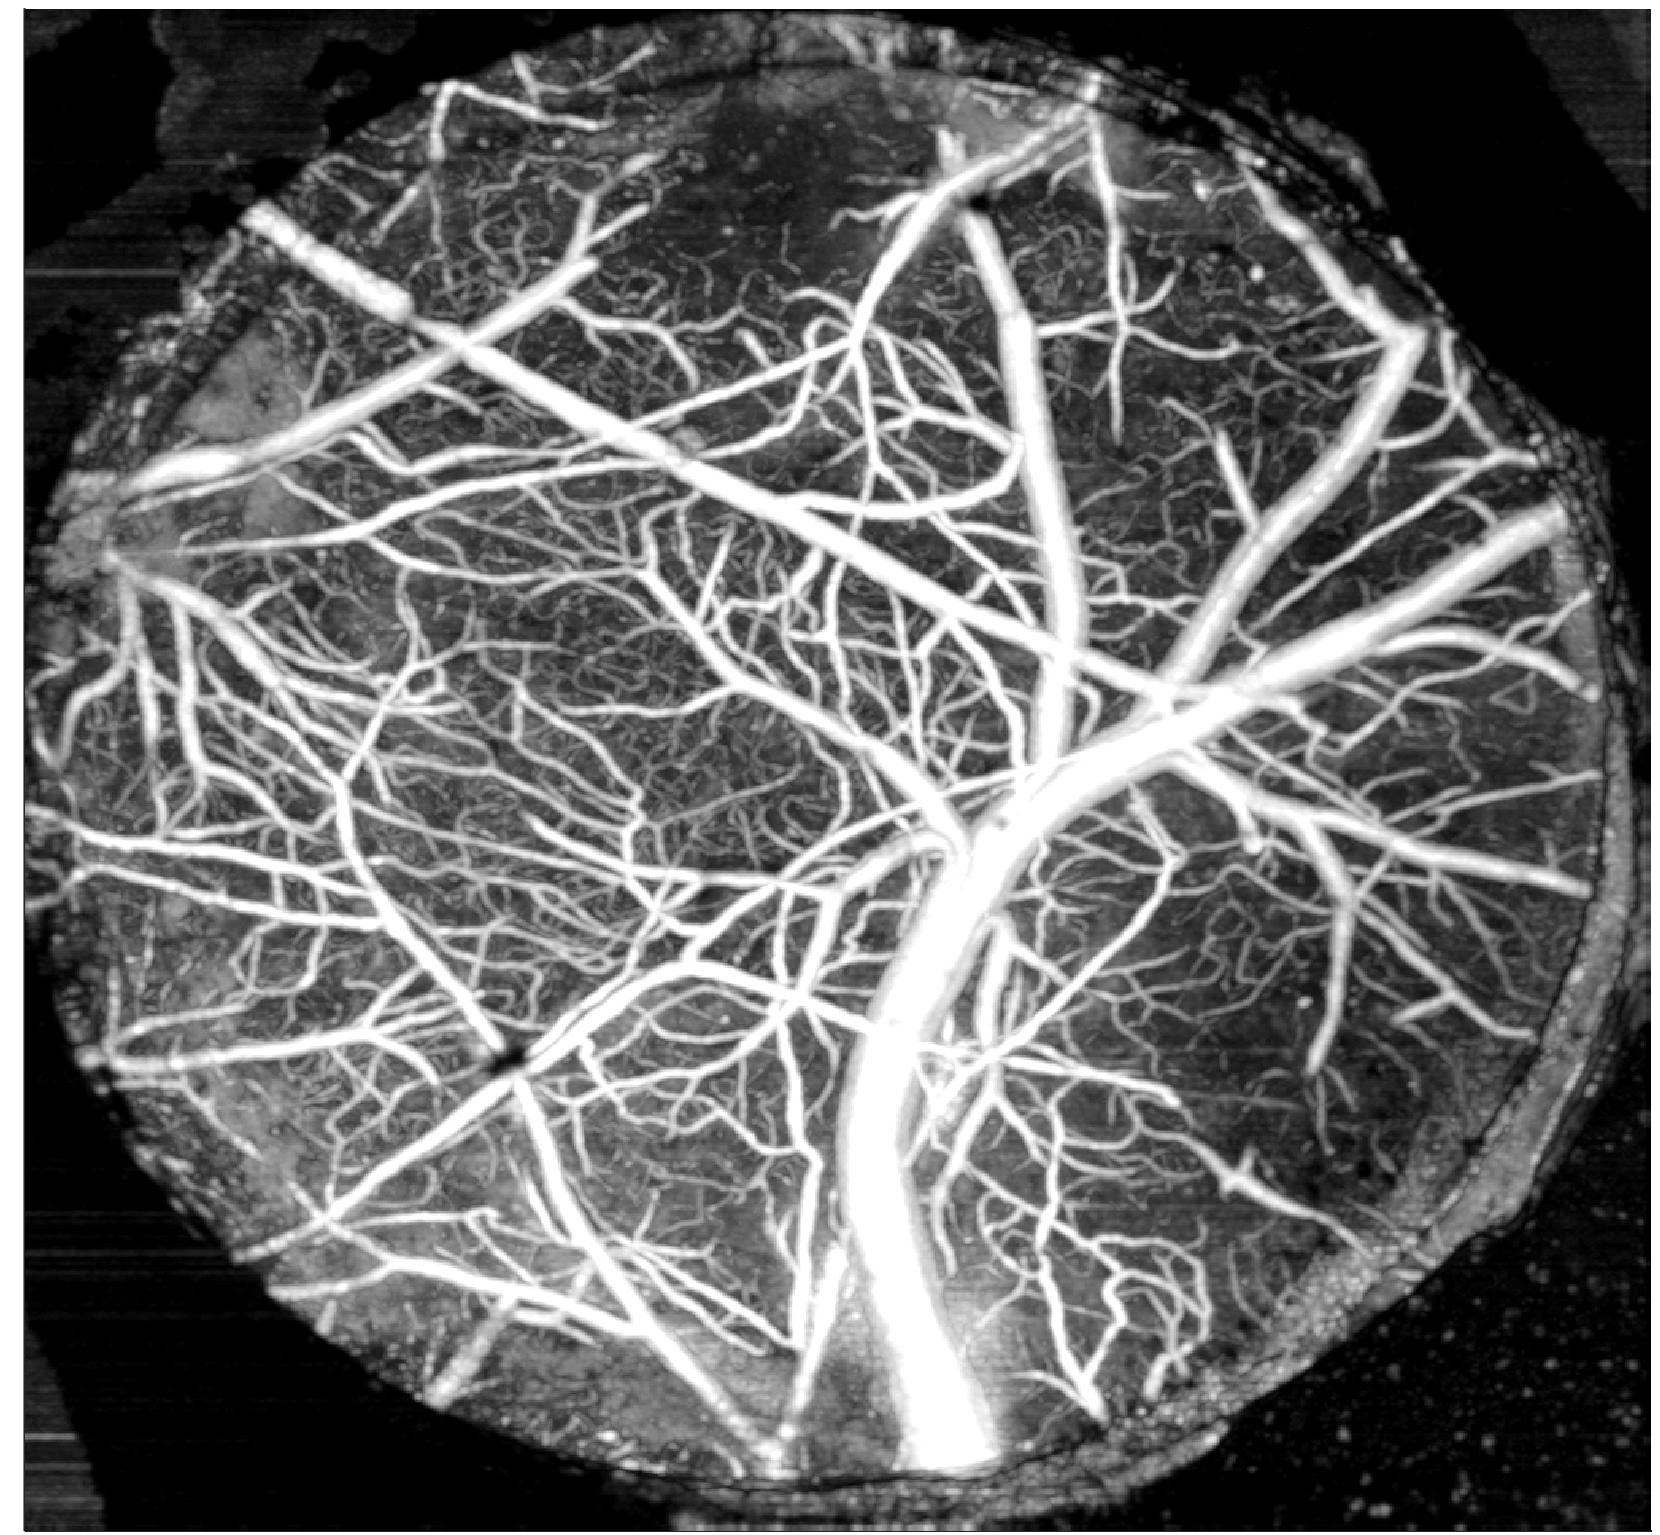

視網膜成像(如下圖):

圖注:SD-OCT在小鼠視網膜成像中的應用示例,展示了多層結構分辨與定量測量能力。

A:小鼠頭部固定在成像裝置上,保證掃描穩定性

B:視網膜掃描定位示意圖

C:小鼠視網膜橫截面圖,清晰標注NFL、IPL、INL、OPL、ONL、ELM、IS/OS、RPE等層結構

D/E:通過分層分析與邊界提取,精確測量不同區域的視網膜厚度,為青光眼、視網膜變性等疾病的早期診斷和療效評估提供數據支持